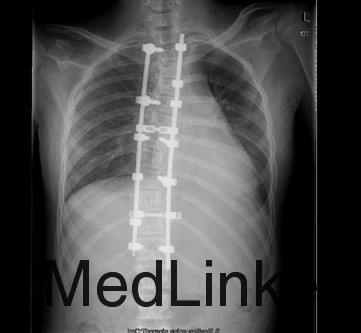

初步诊断:特发性脊柱侧凸(Lenke:ⅡA ̄型) 诊疗计划: 拟经后路脊柱侧凸矫形+同种异体骨植骨+椎弓根螺钉内固定术术

术中见胸椎脊柱S形侧弯,肌肉韧性较差,棘突偏离中线,凹侧小关节退变明显,胸段脊柱以T8为中心明显右凸,T4为中心向左侧凸起,右侧剃刀背畸形。